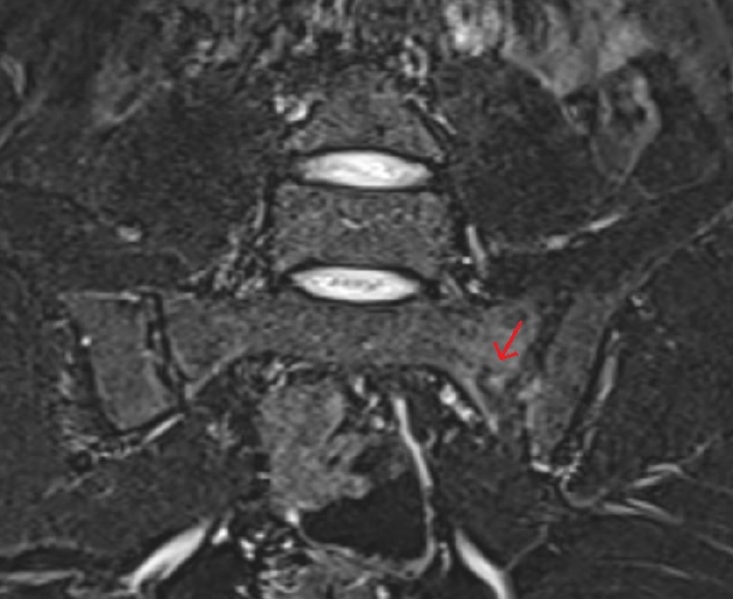

A 23-year-old male student presented with low-back pain. He denied trauma and did not report a clear recent change in training or impact activity, which contributed to an initial diagnostic focus on SI pathology. Pelvic radiography raised concern for a possible SI joint abnormality, and SI MRI was subsequently obtained. The MRI was initially interpreted as unremarkable. On careful retrospective review of the sacrum, a sacral stress fracture pattern involving the sacral ala was identified and subsequently confirmed in consultation with radiology. The MRI protocol included coronal STIR and fat-suppressed T2-weighted sequences with coverage of the sacral wings, enabling detection of characteristic bone marrow edema patterns (

Fig. 2). Laboratory testing did not suggest overt metabolic bone disease, with calcium and parathyroid hormone levels within reference ranges, borderline or low-normal 25-hydroxyvitamin D levels, and age-appropriate DXA Z-scores. At an 8-week follow-up, pain had resolved, and the patient had returned to daily activities.

Fig. 2.Sacroiliac magnetic resonance imaging (patient B). Retrospective review of the sacrum reveals a sacral ala stress fracture pattern with marrow edema, despite an initially unremarkable report. The arrow indicates bone marrow edema in the sacral ala with a visible fracture line.